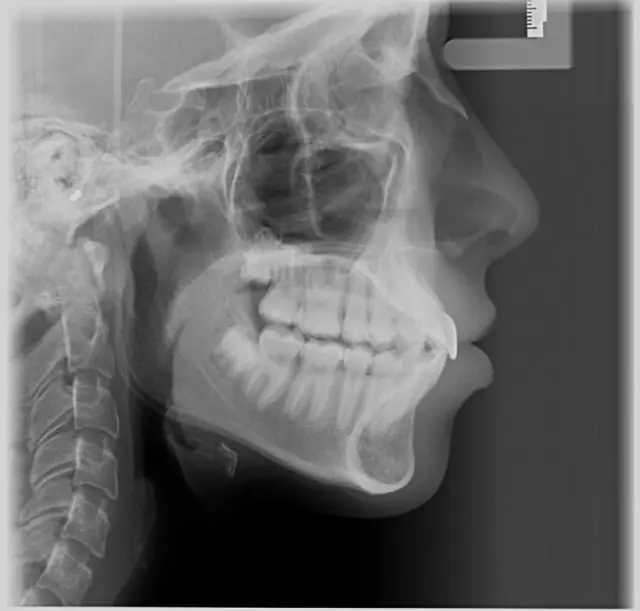

Vršimo usluge snimanja zuba u 2d varijanti. U radu koristimo najprecizniju i najsavremeniju tehnologiju, tako da dobijate kompletan snimak cele vilice ili detaljan snimak konkretnog zuba.

Snimanje vršimo sa ALARA konceptom doze zračenja (min. doza za pacijenta da se dobije kvalitetan snimak). Pratimo trendove i tu smo da radimo najbolje za naše klijente.